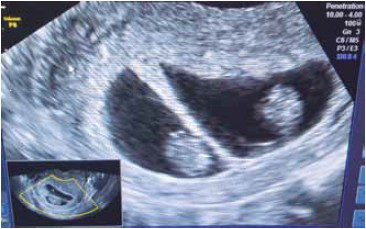

G.C.L., 30 anos, primigesta, veio para consulta de pré-natal, com laudo do primeiro ultrassom, com idade gestacional pela biometria do diâmetro cabeça nádega de 9 semanas.

De acordo com a imagem, assinale a alternativa contendo o diagnóstico correto.